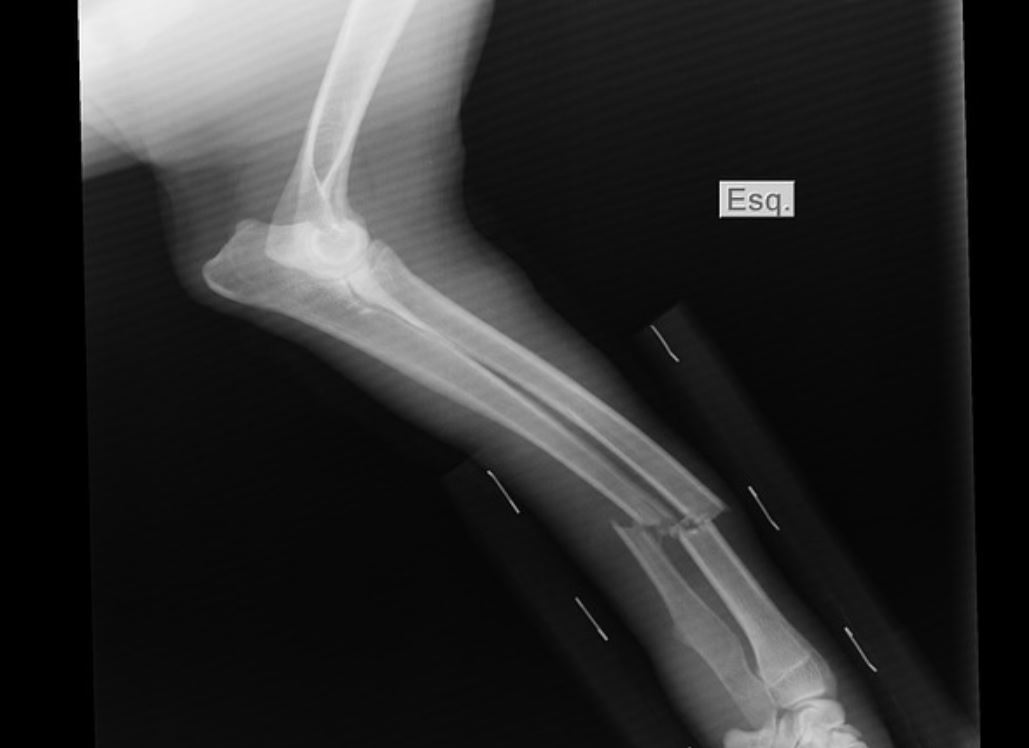

Una mujer de 40 años resultó con una fractura en su muñeca izquierda luego que un hombre la golpeara con un fierro tras un choque.

En medio de los insultos, el hombre la golpeó y le produjo la fractura, según informó Crónica.